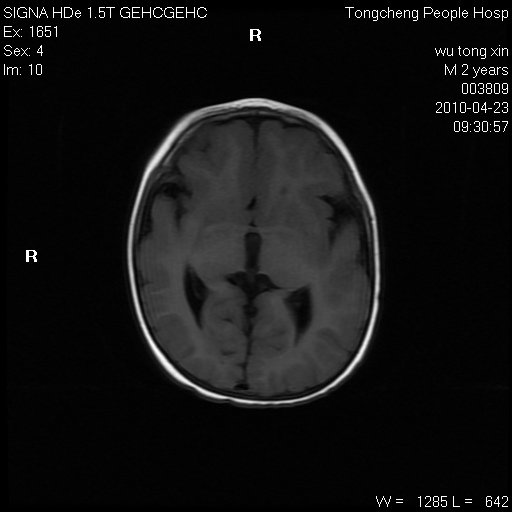

以下是引用赵物学在2010-4-25 12:43:00的发言:[br]巨脑回[br]侧脑室后角低密度影考虑hie或肾上腺脑白质营养不良?[br][br][本贴已被 赵物学 于 2010-4-25 12:51:28 修改过]

以下是引用gaoxiao在2010-4-25 16:54:00的发言:[br]巨脑回畸形。脑白质髓鞘化不良

以下是引用pujunzhi在2010-4-25 21:35:00的发言:[br]考虑 1双侧大脑皮质发育不良 2轻度脑积水 3双侧脑室后角旁片状长t1长t2信号,需继续观察,因为正常小儿此处脑白质的髓鞘化时间可以延迟到4-6岁,才显示正常。